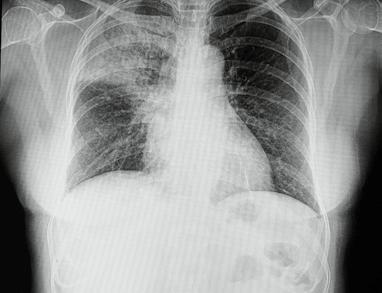

Wanneer een patiënt op intensieve zorg terechtkomt, wordt de bloeddruk, zuurstofsaturatie in het bloed, lichaamstemperatuur, bloedglucoseconcentratie, … constant gemonitord. Deze vitale parameters worden allemaal door homeostatische regelmechanismen relatief stabiel gehouden. Ernstige afwijkingen van de vitale parameters kunnen wijzen op een levensbedreigende aandoening. Om de cellen (en dus de organen) te beschermen, zullen de artsen deze parameters zo snel mogelijk corrigeren. Artsen bewaken de homeostase bij een patiënt en sturen bij waar nodig.